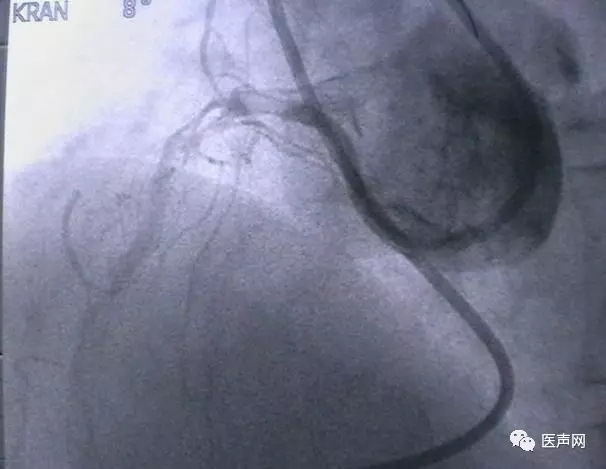

病例6:小血管病变处理---药物涂层球囊+金属裸支架(DCB+BMS)

中间支PCI术后,复查CAG,无ISR。RCA远端90%狭窄,小血管病变,中段40%狭窄 处理:小血管病变处理策略---药物涂层球囊+金属裸支架(DCB+BMS)(附图)

DCB(Eurocro, DIOR):2.5×15@8-10bar,2min

BMS(Motion): 2.5×18@14bar,20sec

药物涂层球囊扩张

支架术后

这是余江涛教授刚刚开始做的新课题,用DCB治疗小血管病变(small vessel lesion)。